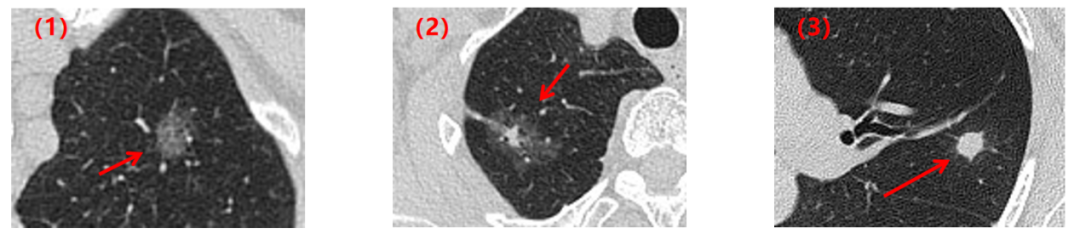

肺结节到底是不是肺癌?

这是大家最关心的事了,我们来看几组肺结节随访病例模式图。

第一组:实性结节

患者1:2019年左肺发现一枚实性肺结节,两年后CT复查,肺内的这枚实性结节大小和形态没有明显变化。

患者2:2019年左肺发现一枚实性肺结节,两年的CT复查,肺内的这枚实性结节逐渐变小至消失不见了。

患者3:2016年右肺发现一枚实性肺结节,两年后复查CT,这枚结节明显增大,形态逐渐不规则,最后病理结果提示为肺癌。